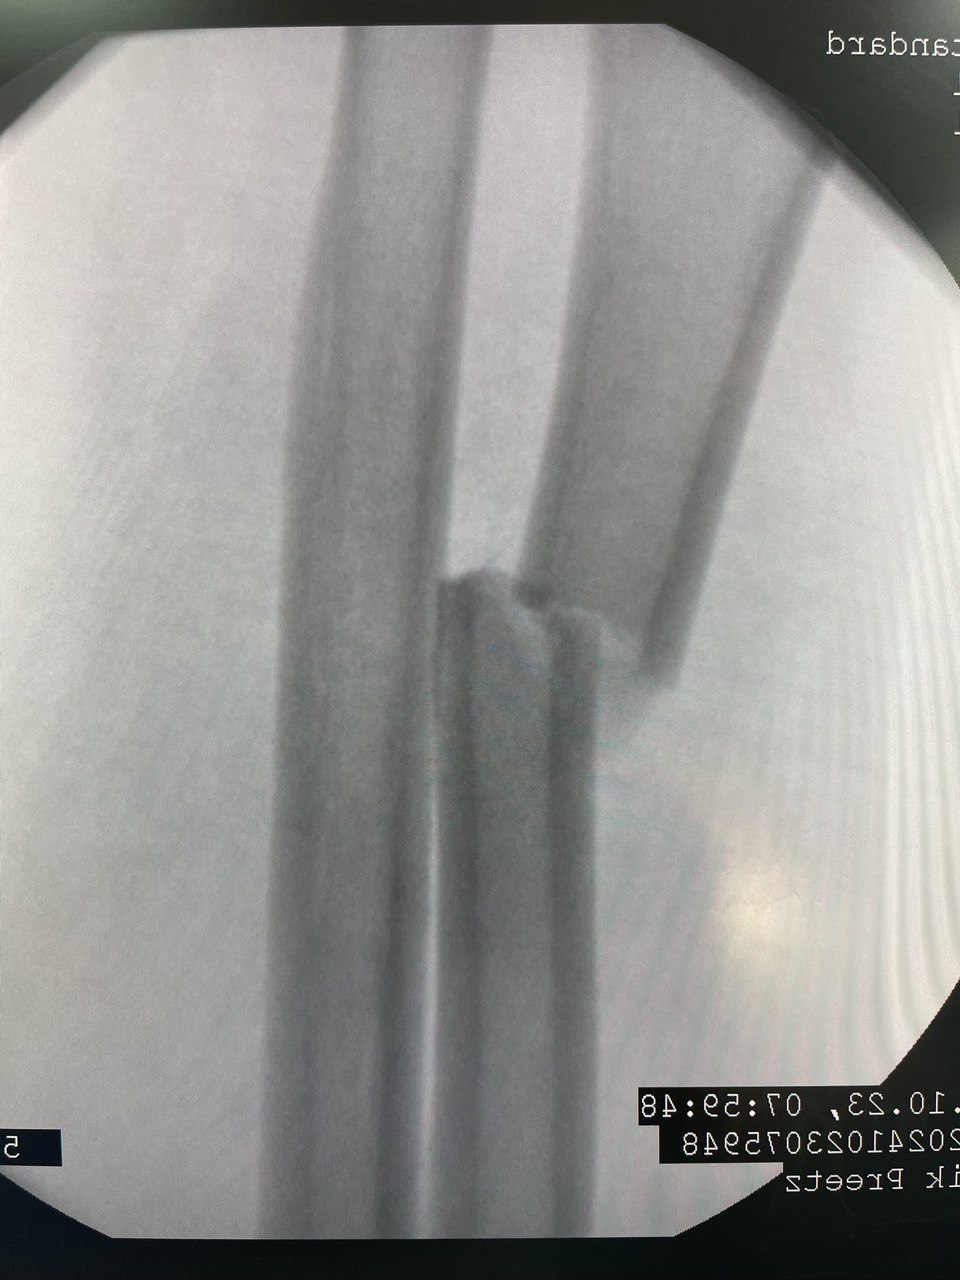

Клинический случай: перелом диафиза лучевой кости

Клинический случай с повреждением диафиза лучевой кости и последовательным контролем состояния.